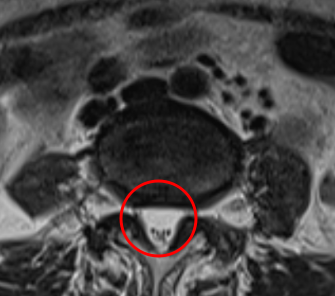

治療前

腰椎MRIを確認したところ、赤い枠で示されているL4/5に部分に脊柱管狭窄症を認めました。またこの腰部脊柱管狭窄症は、腰部すべり症が原因であると考えられます。